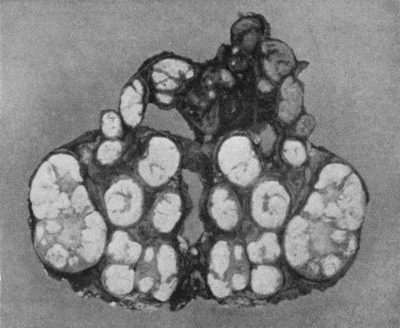

168.Multiple partially ossified Chondromas of Synovial Membrane from Shoulder-joint 542

169.Multiple Cartilaginous Loose Bodies from Knee-joint 543